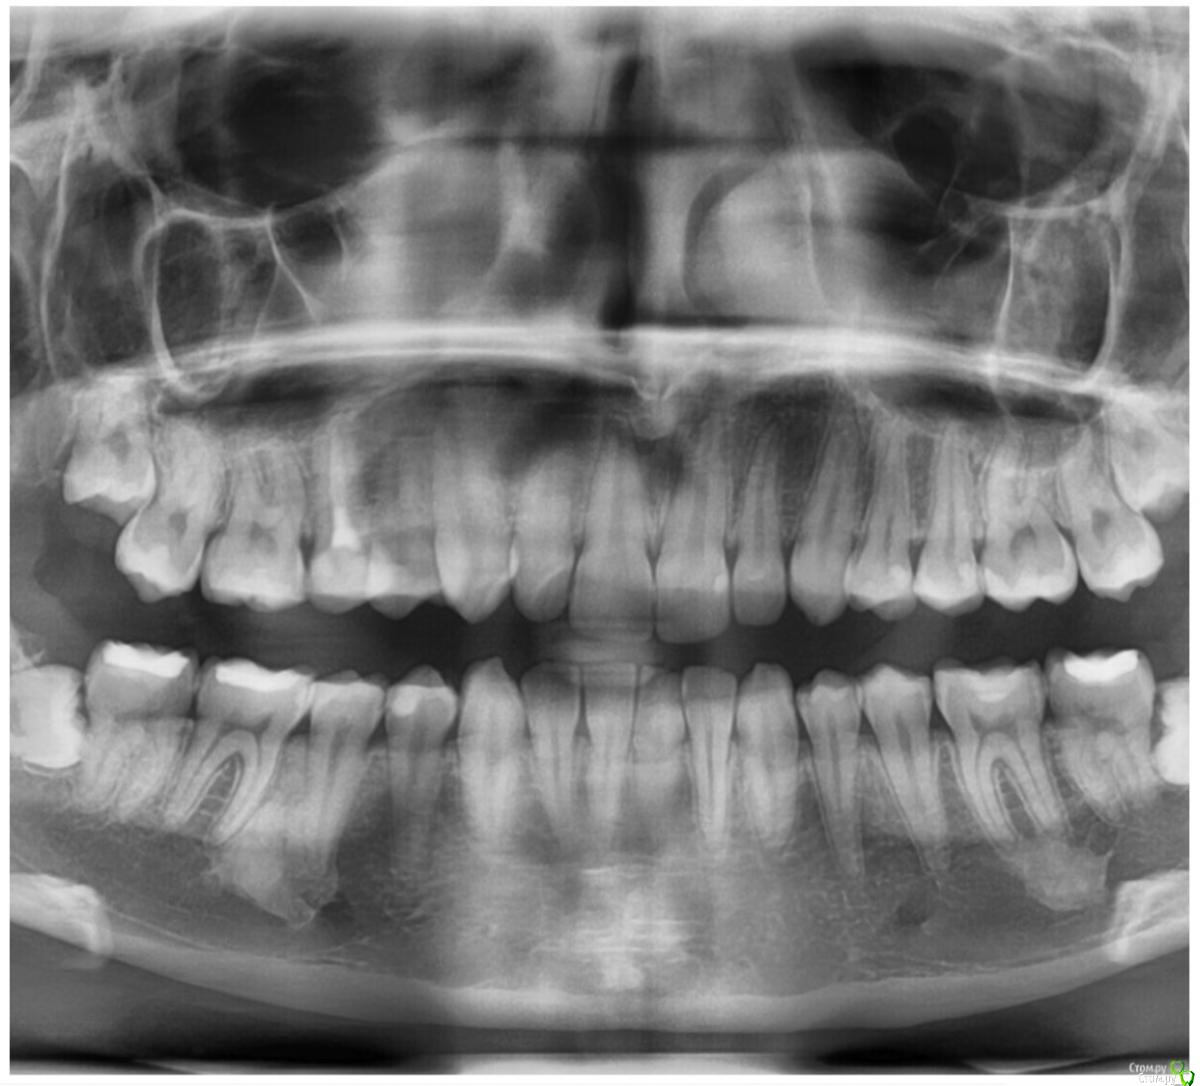

Остеома,гиперостоз,опухоль?

Я хочу устанавливать брекеты,мне сделали снимок и обнаружили два пятна слева.Скажите пожалуйста опасно ли это? Делала КТ в том числе. Нужно ли это удалять?

И стоит ли мне ставить брекеты? Что худшее может быть? Я очень очень сильно переживаю.

Сказали, что такое очень редко встречается.